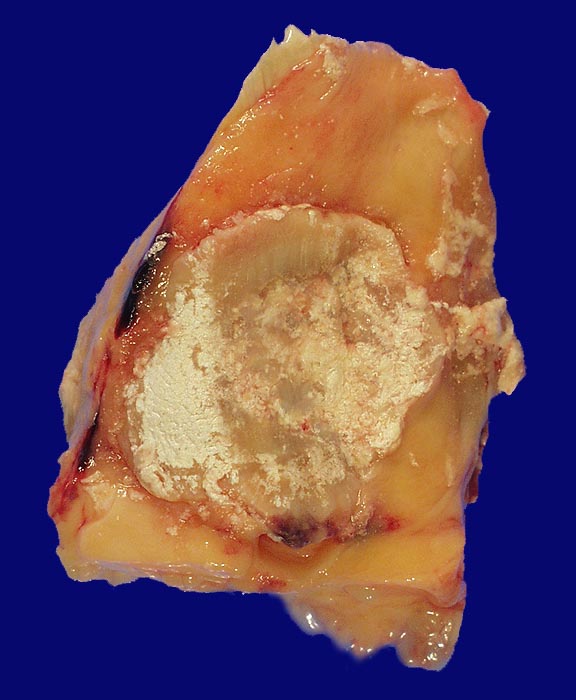

Bei einer Gicht sind kristallin ausgefällte Natriumuratkristalle in den neutrophilen Granulozyten des Gelenkergusses und kalkweisse Auflagerungen am Gelenkknorpel nachweisbar. Kristallablagerungen in Form von Gichttophi mit einer granulomatösen Fremdkörperreaktion finden sich ausserhalb von Gelenken auch in Sehnenscheiden (Achillessehne), Weichteilen (Ohrläppchen, Ellenbogen, Knie), in der Achillessehne oder im Nierenparenchym. Die Löslichkeit von Harnsäure nimmt mit der Umgebungstemperatur ab, sodass die Kristallablagerungen vorwiegend peripher vorkommen. Am häufigsten betroffen ist das Grosszehengrundgelenk (Podagra), gefolgt von Sprunggelenk, Ellenbogengelenk, Kniegelenk und anderen Gelenken an Fuss und Hand.

Die nadelförmigen und zu Büscheln angeordneten Natriumuratkristalle zeigen im polarisierten Licht eine starke Doppelbrechung, sind aber wasserlöslich und daher in den üblichen histologischen Schnitten nach Formalinfixierung nicht oder allenfalls noch residuell nachweisbar. Die ebenfalls doppelbrechenden, nicht wasserlöslichen Kalziumpyrophosphatkristalle der Pseudogicht sind kürzer und oft rhomboid geformt.